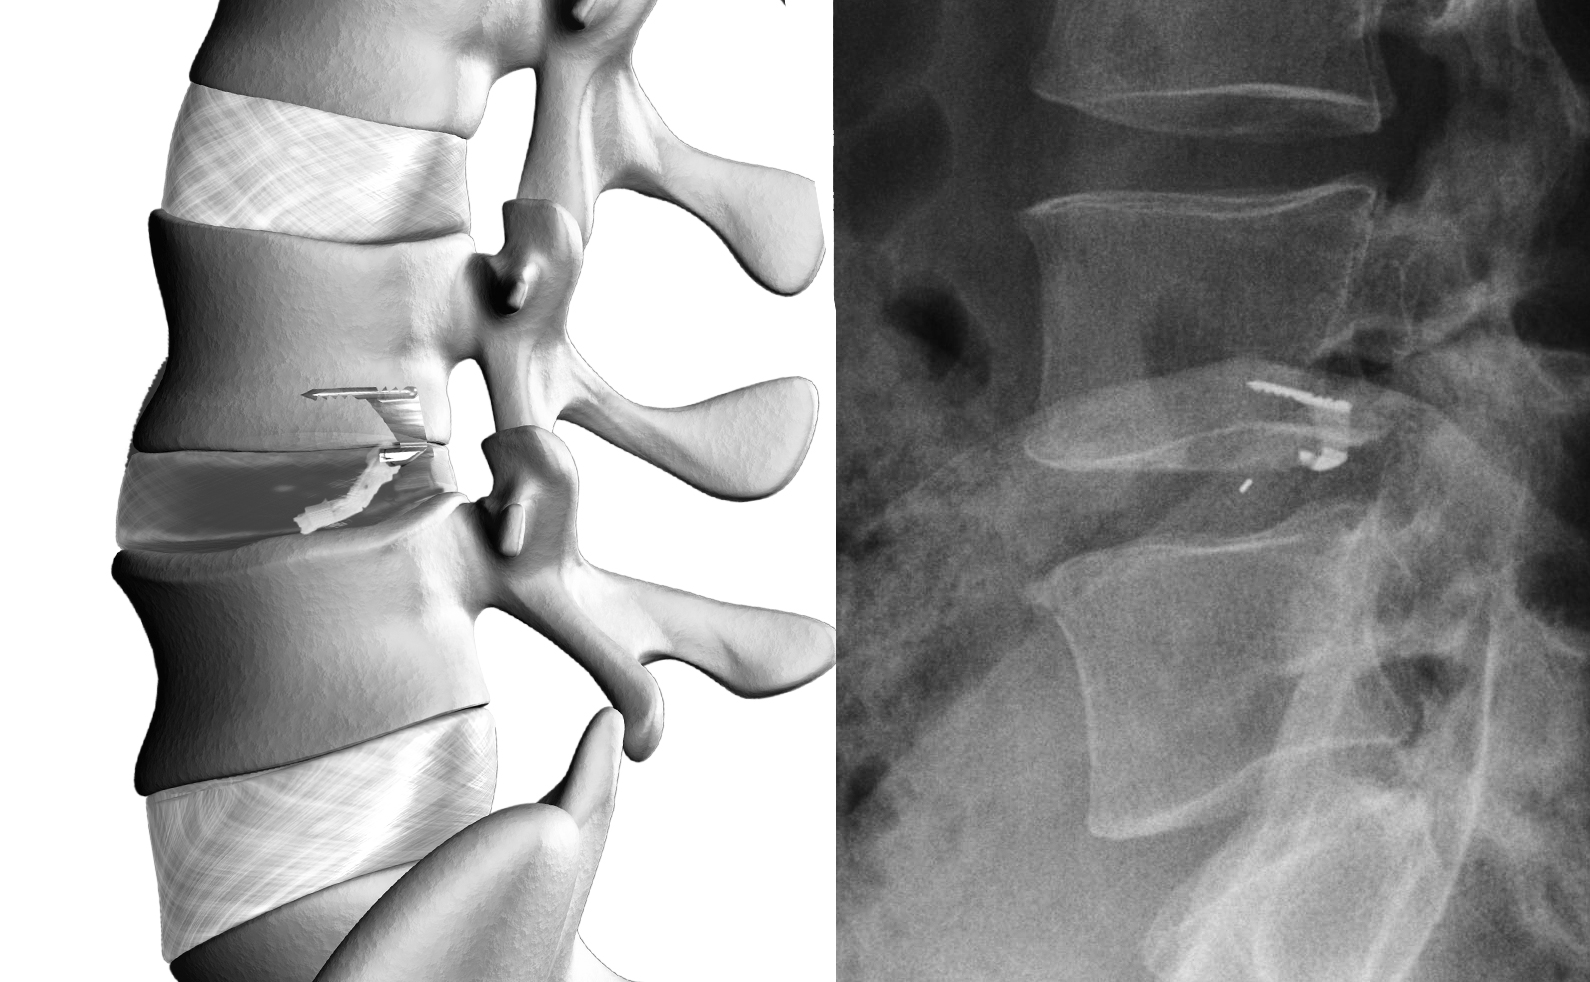

Barricaid is a small implant, slightly larger than a pencil eraser that is designed to plug the larger holes in the disc wall. It is made up of a titanium bone anchor which secures the polymer plug into the disc space to repair and reconstruct disc wall. Barricaid has been shown to reduce the need for a second operation by 81%1.

When a disc herniates, it’s because a hole or weakness has developed in the wall of the disc and the material inside the disc has been pushed out. The surgeon performs the discectomy though this access point.  If a large hole is left open, there is a 27%2+ chance of reherniation and the return of pain and symptoms. Barricaid is design to close the hole by creating a barrier against reherniation.